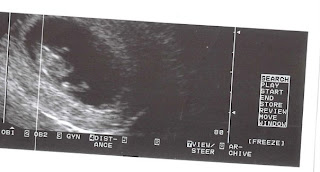

WE'RE HAVING A BOY!!!!

we had our big ultrasound the day before Thanksgiving! My parents and my little sister got to be there with us :) It was so exciting to see how much our baby has grown, he looks so cramped up in there! I'm so excited for April to get here so I can finally hold my little man! We havent completely decided on a name yet...but we're getting there. I'll try to give more updates and things happen :)